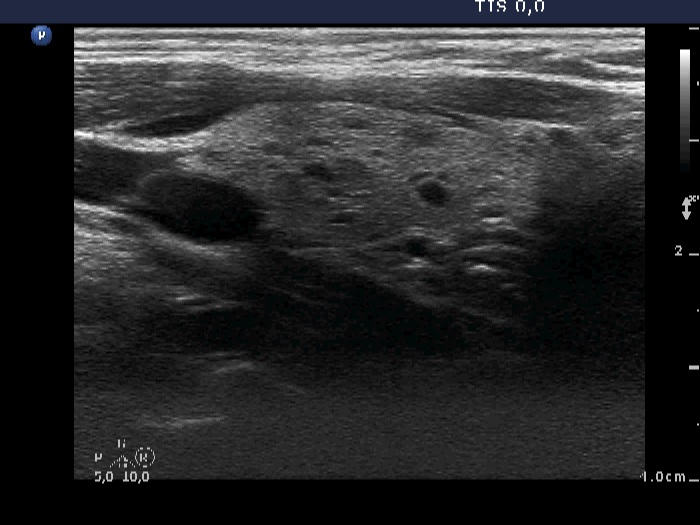

Intranodular hyperechogenic figures - case 1108 (ultrasonographic picture 4)

Left lobe, longitudinal view. There are moderately hypoechogenic areas together with more hypoechogenic lesions. The former correspond to the underlying autoimmune thyroiditis while the latter may be presentations of evolving cystic hyperplastic nodules.